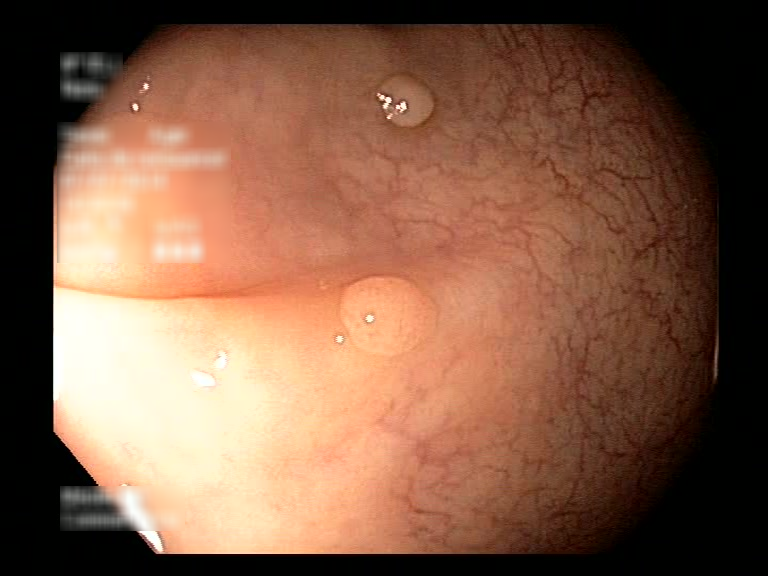

| Lesion | White Light Frame | NBI Frame | White Light Video | NBI Video | Camera Calibration |

| hyperplasic_01 |  |

|

WL.mp4 | NBI.mp4 | cam.xml |